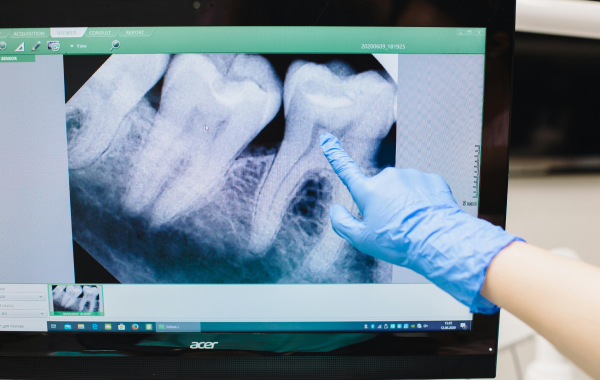

Le rôle de la radiographie et du microscope

Le retraitement endodontique s’appuie sur des outils de précision. Les radiographies numériques permettent de visualiser la structure interne de la dent et de localiser les zones d’infection. Le microscope opératoire améliore la visibilité des canaux étroits ou calcifiés et facilite le retrait des fragments d’instruments. Ces outils contribuent à la précision du geste et à la réussite du retraitement.